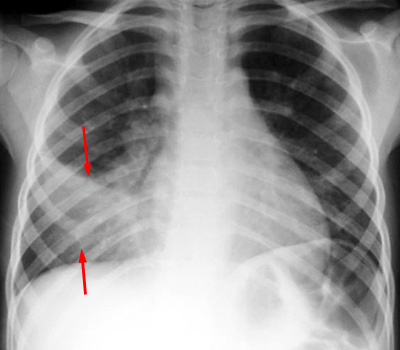

| Example of a right middle lobe pneumonia. PA and LAT CXR demonstrate consolidation in the right middle lobe. |